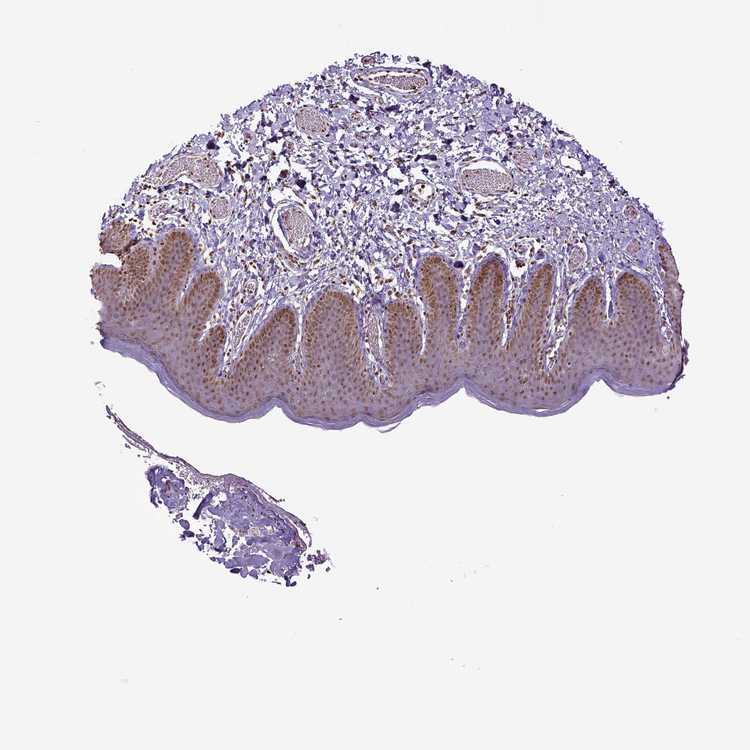

SKIN 1 - Antibody stainingi

Antibody staining in the annotated cell types in the current human tissue is reported as not detected, low, medium, or high, based on conventional immunohistochemistry profiling in selected tissues. This score is based on the combination of the staining intensity and fraction of stained cells.

Each image is clickable and will lead to virtual microscopy that enables deeper exploration of all samples and also displays staining intensity scores, fraction scores and subcellular localization as well as patient and tissue information for each sample.

Antibody HPA004705

Langerhans High

Fibroblasts High

Keratinocytes Medium

Melanocytes Medium